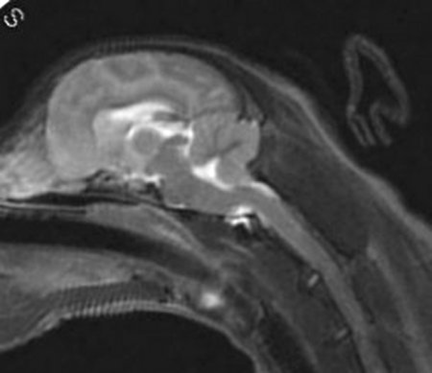

3 years old

No symptoms of SM

Mildest possible form of malformation, if

any

Very mild herniation of cerebellum

Cerebellum about as full as a Cavalier's

gets

Medulla almost normal

No syrinxes present

Note this dog had another MRI at 14 years of age due to a

stroke.

He had zero SM and all else looked the same.